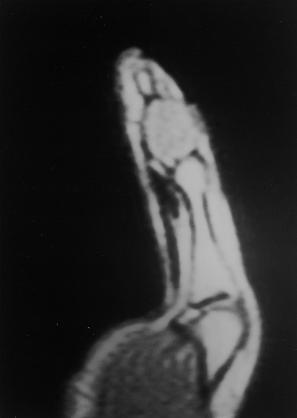

https://upload.orthobullets.com/topic/8018/images/ollier foot.jpg

• the most common locations hand (60%) > feet

• cortical expansion and thinning may be present in hands, feet (inherited diseases)

• Ollier's disease

• bones are dysplastic, with shortening and bowing